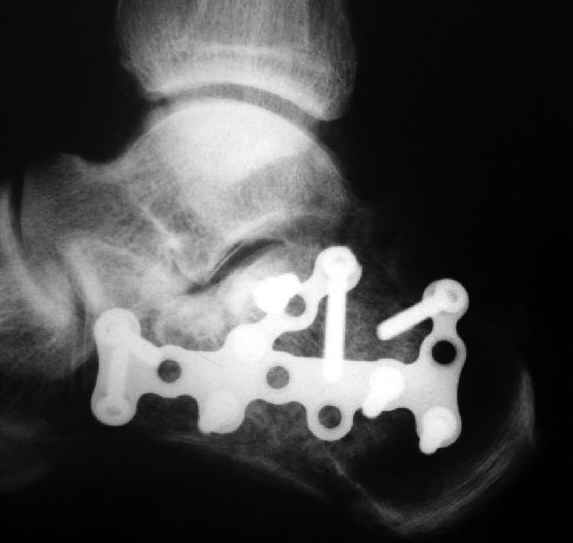

Окончательная фиксация спицами, пяточными пластинами (5) , в последнее время стали применять крючковидные пластины (ДЕОСТ) (6,6a).